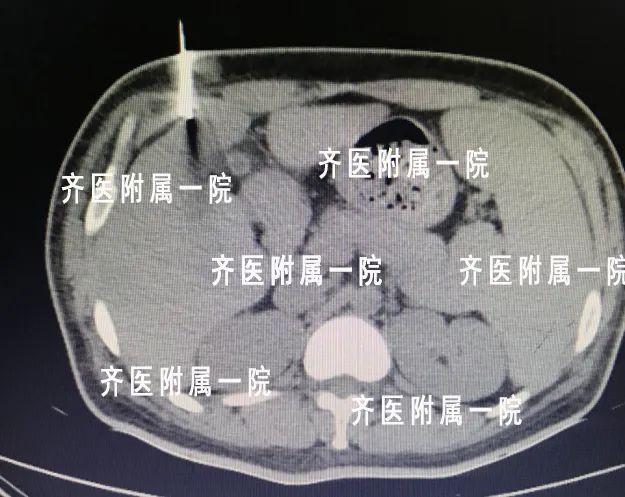

近年来肿瘤的发病年龄越来越年轻化,大家已经开始逐渐重视它。穿刺活检是肿瘤治疗过程中非常重要的一步,肿瘤患者需要选择那些手段治疗,往往有赖于穿刺活检得到的病理结果。首先:看片子做出的诊断叫做“影像学诊断”,只能凭经验初步判断是不是肿瘤,但是具体是哪一种类型的肿瘤,有没有基因突变都不得而知,后面的治疗用药也会盲目。所以,穿刺以后得到的病理结果是医生确诊的金标准,比如下面肿瘤科的这个患者:

国内外大量的研究证明,在操作中恰当的保护措施,种植转移的概率完全可以忽略不计,尤其我们肿瘤科开展的同轴活检技术,更是大大避免您的忧虑。以前的活检技术直接穿刺扎到肿瘤,容易造成“拔起萝卜带泥”,现在的我院开展的同轴活检技术,只需要进针一次,多次多角度取材,同时进行针道封堵,取材量比以前要大,避免了针道转移,减少患者痛苦!